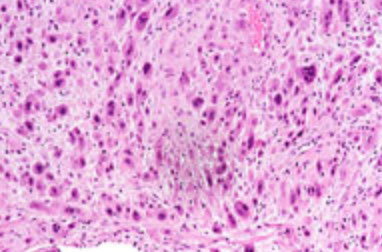

Epithelioid Trophoblastic Tumor (ETT)

Arises from chorionic-type intermediate trophoblastic cells

- b-hCG should not be as elevated as in chorioca ((?? per Webpath.com, levels of hCG are elevated ??)

Micro: atypical cells, tends to have a pushing pattern (vs PSTT which is infiltrative), very cellular and geographic necrosis,

IHC: (+) p63 (very strong pos), inhibin, CK18, Cyclin E (strong pos), hCG, HLA-G

- neg: hPL (var), Mel-CAM (var)

- low Ki67 (>10%, <25%)

Epithelioid trophoblastic tumor. Tumor made of intermediate trophoblastic cells in nests and sheets in a hyaline matrix